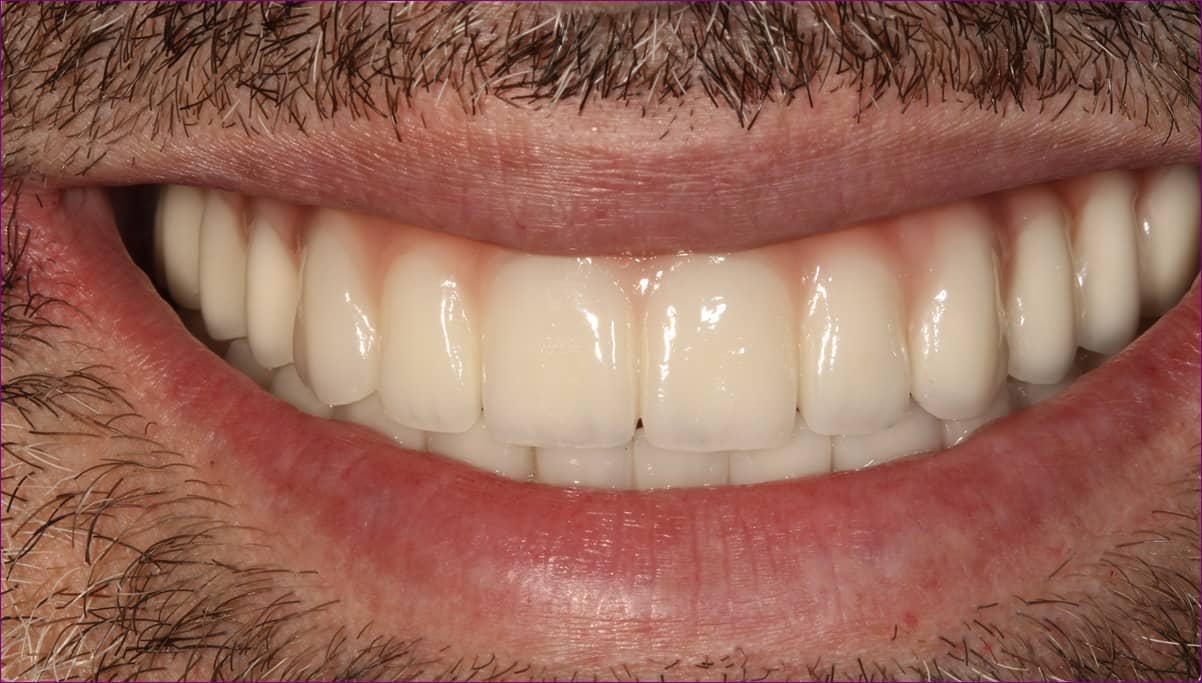

Az elkészült pótlás

A becsavarozott, átadott alsó-felső rögzített pótlás röntgenfelvétele az alább látható.

Páciensünk a kezelés során végig együttműködő és türelmes volt, a végeredménnyel pedig maximálisan elégedett volt.

Boldog mosolyán mindez vissza is tükröződik!